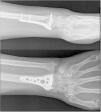

Intervención: Luego de 7 días del trauma se le practicó reducción abierta más osteosíntesis con placa de bloqueo volar (fig. 1), en control de ortopedia a los 15 días del posquirúrgico presenta limitación funcional total de mano y muñeca derecha, ocasionada por el dolor y el edema. Después de 17 días del posquirúrgico inició el proceso de rehabilitación, asistió a 10 sesiones de terapia física y a 12 sesiones de terapia de movilización pasiva con órtesis robótica (fig. 2).

Resultados: inicialmente se encontró una puntuación en la escala DASH de 55.3 y en la escala EVA de 3; después de 4 semanas de rehabilitación complementada por órtesis robótica, mejoró la funcionalidad según DASH a 5.83 y disminuyó el dolor según EVA a 0. Además, mejoró los arcos de movilidad articular de la muñeca en extensión de 0 a 30 grados, en flexión de 30 a 45 grados, la desviación radial de 10 a 20 grados, y conservó la desviación ulnar en 15 grados. La paciente inició las actividades de la vida diaria luego de la tercera semana de rehabilitación, y no se reportaron eventos adversos durante la intervención. (Tabla I y II)